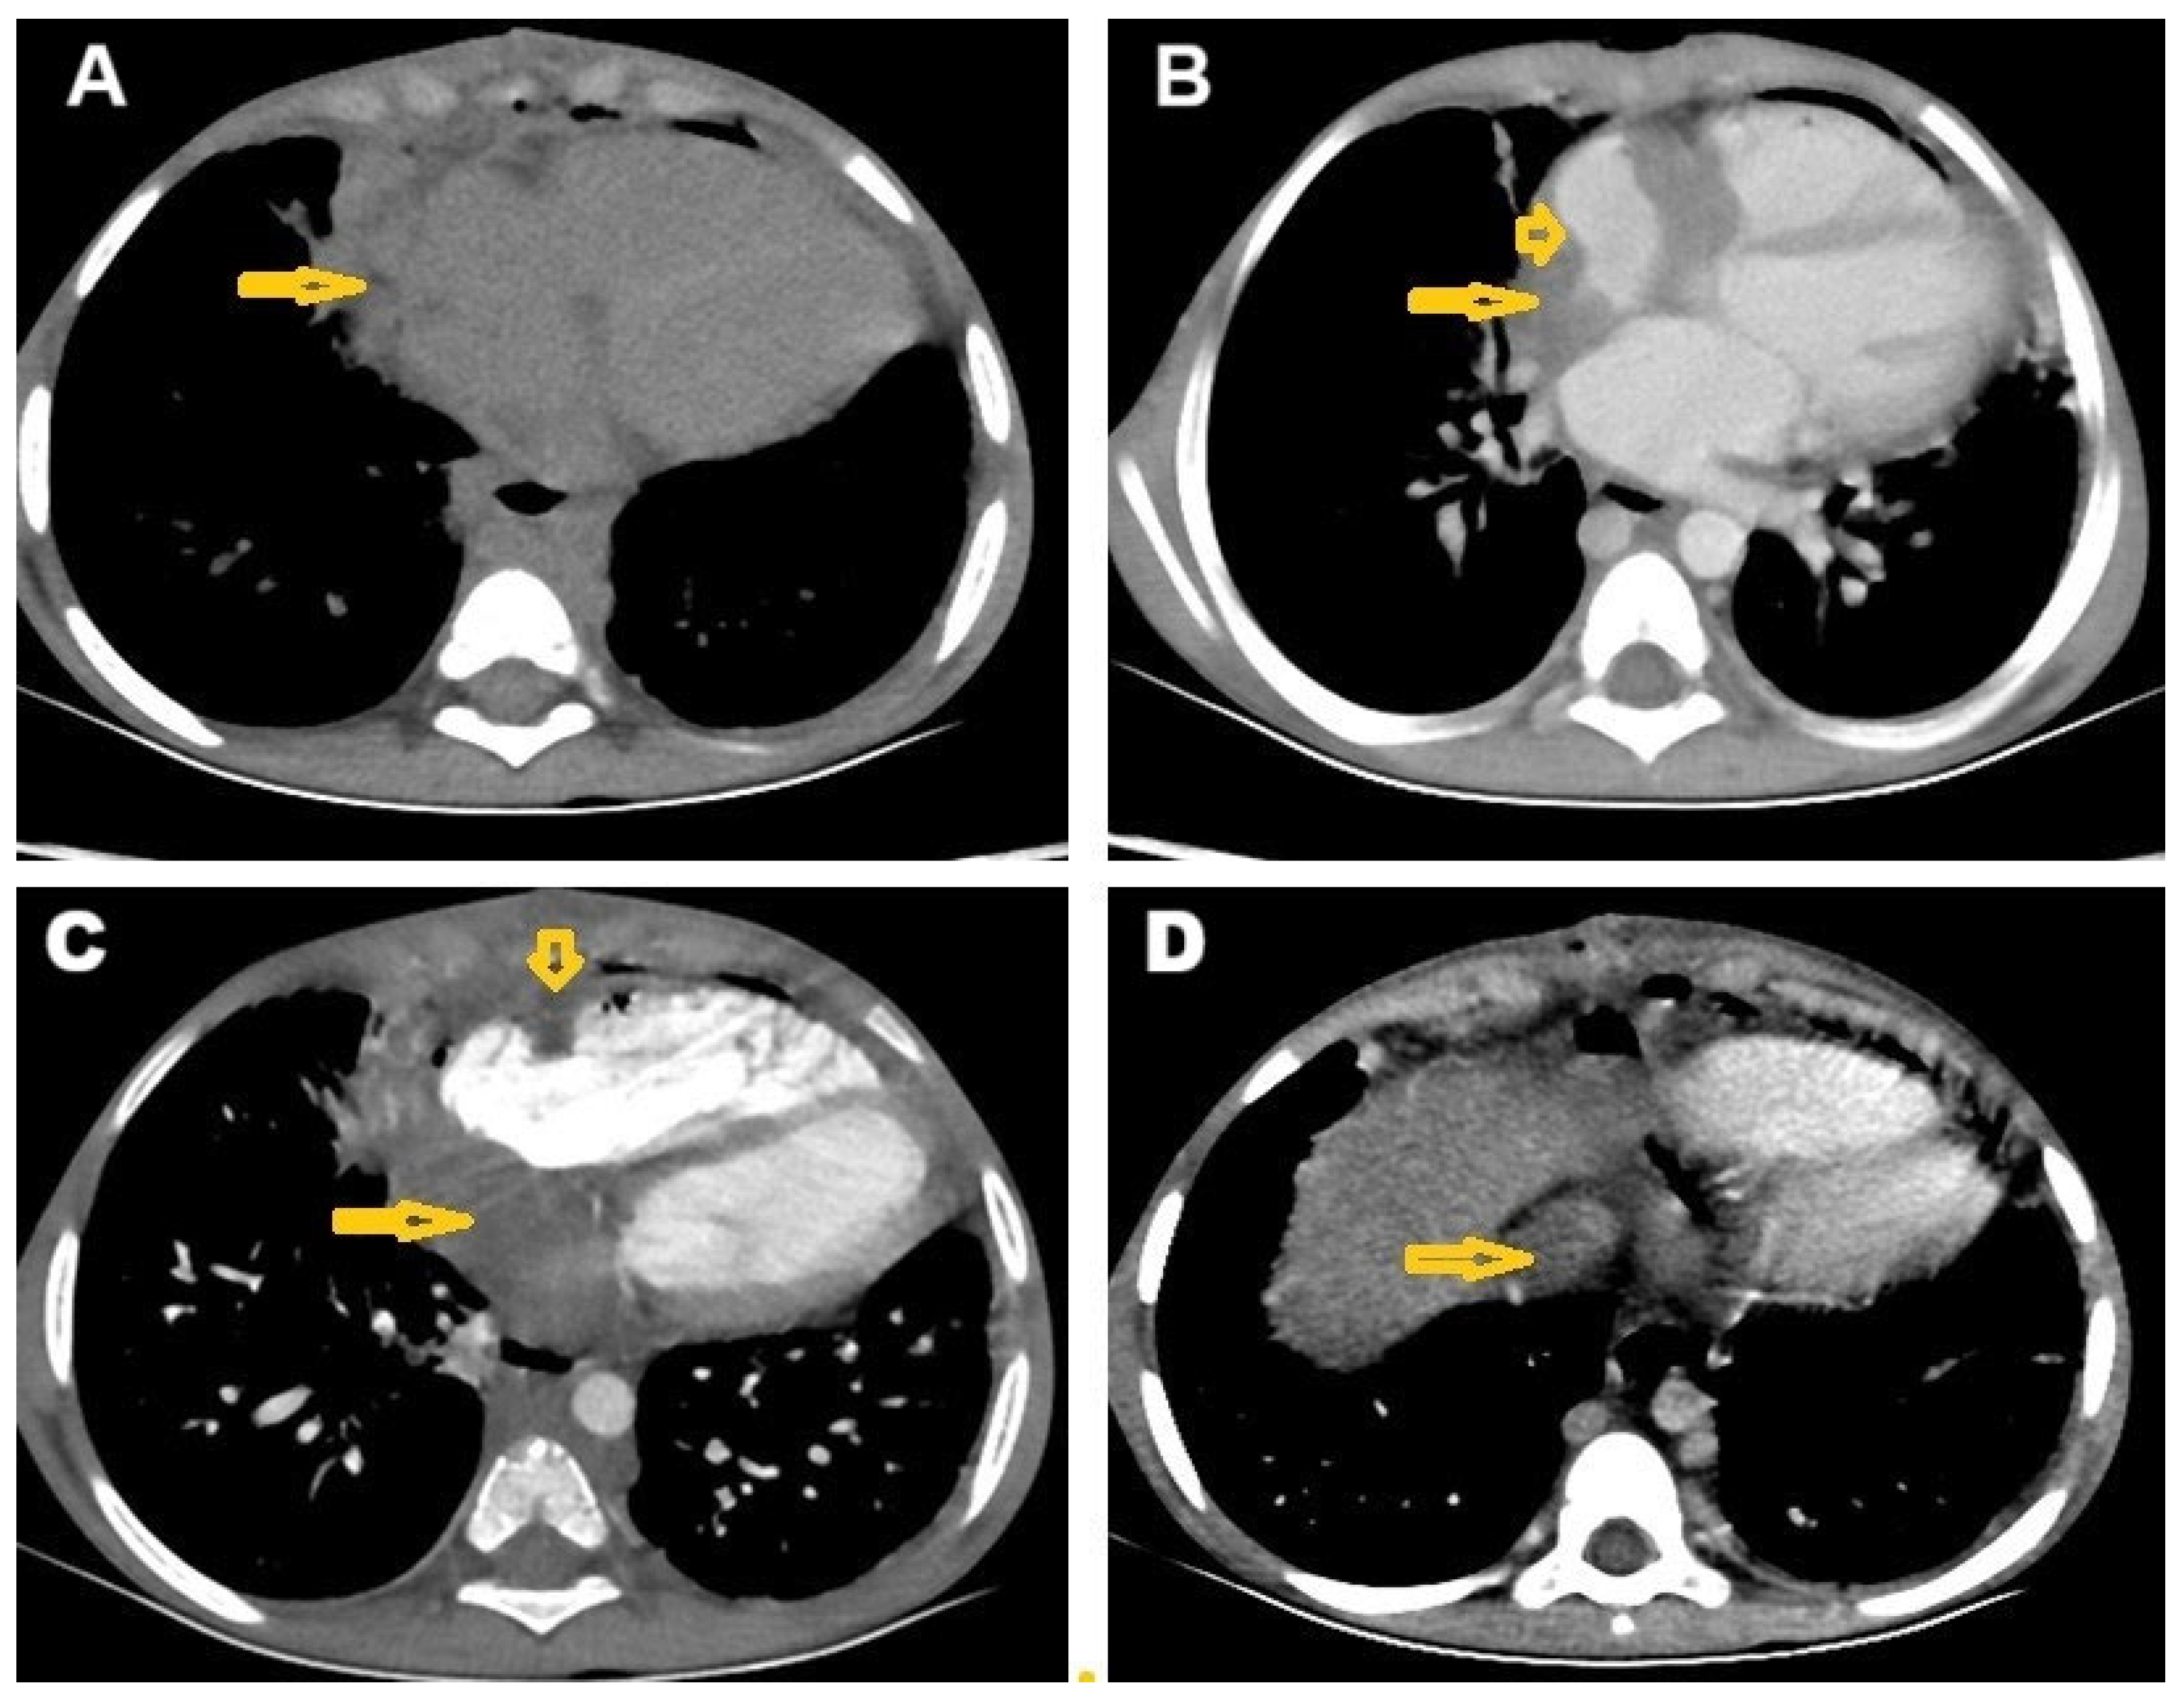

2. Case Presentation